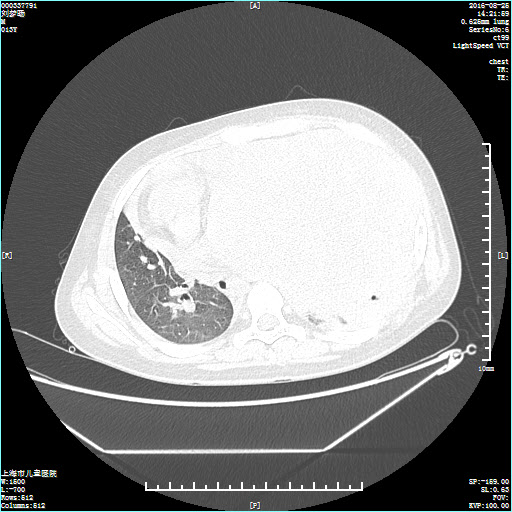

10岁的小文气喘不已,罪魁祸首竟是胸腔内的“包袱”——一个与座机电话大小相仿的肿瘤,几乎占满了孩子的整个左侧胸腔。整整五个小时,小文经历了肿瘤切除术、肺叶修补术、胸膜剥脱术、膈肌折叠术等“四术合一”,最终体内“炸弹”被成功拆除,这个压在患儿一家心上的“包袱”终于卸下。

通过穿刺活检,医生发现,小文的左侧胸膛竟“埋伏”着一个巨大的恶性肿瘤,尺寸约20cm×15cm×5cm,几乎占满了左胸,其肺部与心脏均受到不同程度挤压。可惜,经放化疗,不仅疗效不佳,小文还在诊治过程中出现反复发热。心急如焚的家人带着小文来到上海市儿童医院心胸外科就诊,当时气喘气急的他已经无法平卧。